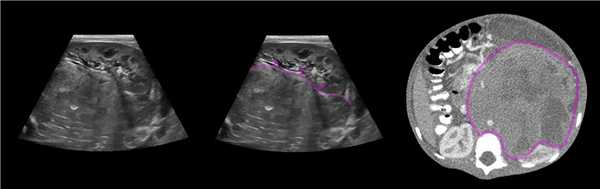

На УЗИ в мочевом пузыре или в уретре определяется анэхогенное образование, округлой формы, с четким и ровным контуром; соответствующий мочеточник обычно заметно расширен; может присутствовать гидронефроз верхней части удвоенной почки. Уретероцеле определяют как внутрипузырные (полностью внутри мочевого пузыря) или внепузырные (некоторая часть постоянно расположена в шейке мочевого пузыря или в уретре).

Рисунок. Внутрипузырный (1) и внепузырный (2) уретероцеле.

Рисунок. У новорожденного на УЗИ почек определяется гидронефроз (1) и расширенный мочеточник (2) справа. В мочевом пузыре двустороннее уретероцеле (3). При исследовании левой почки структурных изменений не выявлено.

Рисунок. На УЗИ определяется удвоенная чашечно-лоханочная система, расширена лоханка верхнего сегмента (1) и мочеточник на всем протяжение (2, 3), в мочевом пузыре уретроцеле (4). Полное или неполное удвоение чашечно-лоханочной системы возможно увидеть с помощью КТ-урографии.

Рисунок. Уретероцеле (стрелка) на УЗИ и КТ.

Рисунок. Дистальный отдел мочеточника расширен, в мочевом пузыре анэхогенное образование с тонким и ровным контуром — уретероцеле.